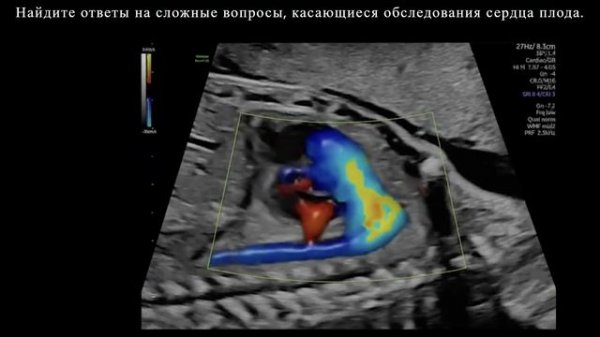

Диагноз. Передовые инструменты для уверенной диагностике на Voluson Expert 22.

Мониторинг дополнительных данных сердца плода на Voluson Expert 22.

Обнаружение. Сердце плода на ультразвуковой системе Voluson Expert 22